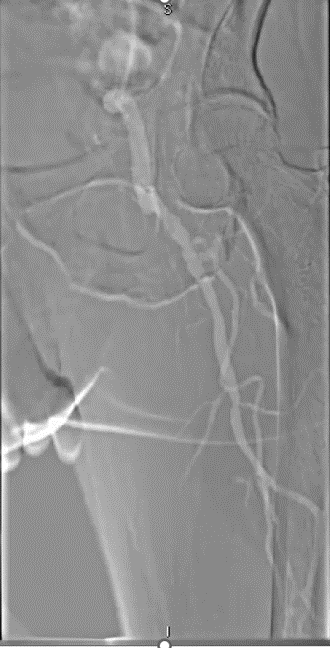

★ Case 2

significantdistal collaterals